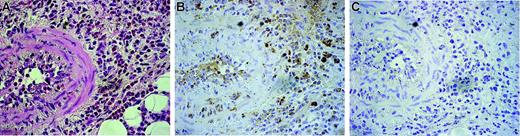

As shown in Figure 1, peripheral eosinophils from CSS patients expressed endogenous DDR1. The DDR1-positive percentage of CSS patients was significantly higher than that of asthma patients and healthy volunteers (Figure 1A-B). The total amount of DDR1 protein was also higher per 1 × 107 eosinophils in CSS patients, and the proportion of cells expressing the DDR1b isoform was also considerably higher in the eosinophils of these patients (Figure 1C-D). There was no significant difference in the concentrations of β1 integrin and another collagen receptor among the 3 groups. Immunohistochemical analysis revealed that the eosinophil staining in the blood vessels and in the wall of the blood vessels was positive for DDR1. Tissue-infiltrating eosinophils also stained positive for DDR1 (Figure 2).

Immunohistochemical analysis of DDR1 expression in the biopsied tissue of a CSS patient. Original magnification, × 350. (A) Hematoxylin-eosin staining. (B) Stained with the DDR1 antibody. (C) Negative control for the DDR1 antibody. Cells were stained with hematoxylin. Images were captured with an Olympus U-PMTVC microscope (Olympus, Tokyo, Japan) with a UPlan Apo 20×/0.80 NA objective lens, and an Olympus DP11-N. Images were captured with Adobe Photoshop 7.0 (Adobe Systems, San Jose, CA).

Biopsied tissues that were obtained from 3 CSS patients were examined by immunohistochemical staining for DDR1 by using a rabbit anti-DDR1 antibody (Santa Cruz Biotechnology) and were visualized by employing the DAB method as described previously.19 Sections 4 μm thick were mounted on poly-l-lysine–coated slides, dewaxed, and washed in Tris-buffered saline (pH 7.4) for 10 minutes. For optimal antigen retrieval, the sections were pressure cooked in 0.01 M citrate buffer (pH 6.0) for 90 seconds. Endogenous peroxidase activity was blocked using a 3% hydrogen peroxide solution in methanol for 10 minutes. Following 2 washes in PBS with 1% saponin, the blocking reaction was performed as reported previously.20 The sections were incubated with a primary antibody solution for 2 hours at room temperature by using a 1:50 dilution of the antibody. The negative control slides were incubated with rabbit IgG (R&D Systems). A secondary biotinylated anti-Ig antibody (R&D Systems) was added, and the mixture was incubated for 30 minutes at room temperature. After washing, the sections were incubated with streptavidin conjugated with horseradish peroxidase (Amersham) and then rinsed with deionized water. The DAB substrate solution was added, and the mixture was incubated for 10 minutes. A brown-colored reaction indicated a positive result.